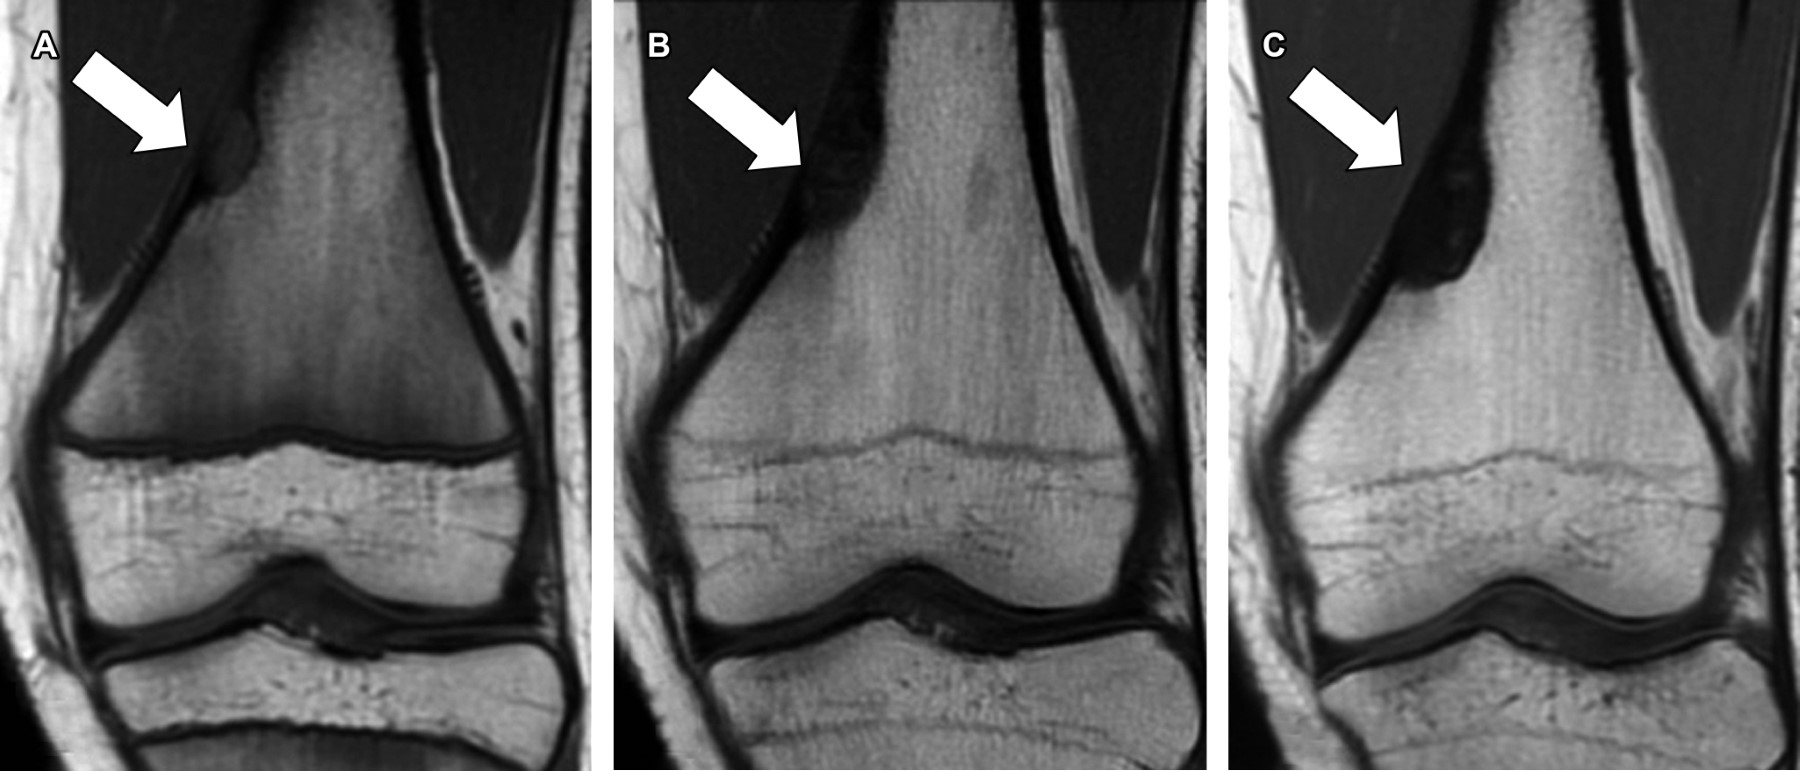

Chronological evolution of bilateral non-ossifying fibroma

Non-ossifying fibroma, a benign bone lesion, is a developmental defect that appears in the metaphyseal region of long bones and advances towards diaphysis secondary to bone growth. These lesions are mainly found in children and predominately in the male gender and are characterized by being asymptomatic; however, their existence predisposes them to pathological fractures. The diagnosis of non-ossifying fibromas is mainly based on their characteristics by imaging methods and is considered "leave alone" lesions due to their benign and self-limiting natural history.

Figure 1